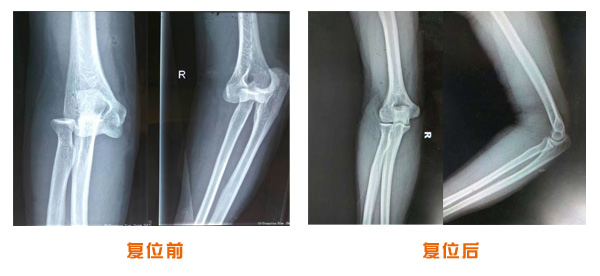

肘關節脫位骨折治療前后對比

尺橈骨克雷氏骨折治療前后